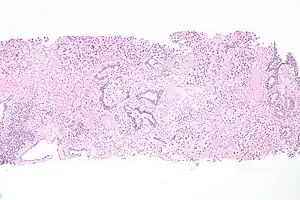

Cancer can also develop in the lining of the urethra.[19] When cancer is present, the most common symptom in an affected person is blood in the urine; a physical medical examination may be otherwise normal, except in late disease.[19] Cancer of the urethra is most often due to cancer of the cells lining the urethra, called transitional cell carcinoma, although it can more rarely occur as a squamous cell carcinoma if the type of cells lining the urethra have changed, such as due to a chronic schistosomiasis infection.[19] Investigations performed usually include collecting a sample of urine for an inspection for malignant cells under a microscope, called cytology, as well as examination with a flexible camera through the urethra, called urethroscopy. If a malignancy is found, a biopsy will be taken, and a CT scan will be performed of other body parts (a CT scan of the chest, abdomen and pelvis) to look for additional metastatic lesions.[19] After the cancer is staged, treatment may involve chemotherapy.